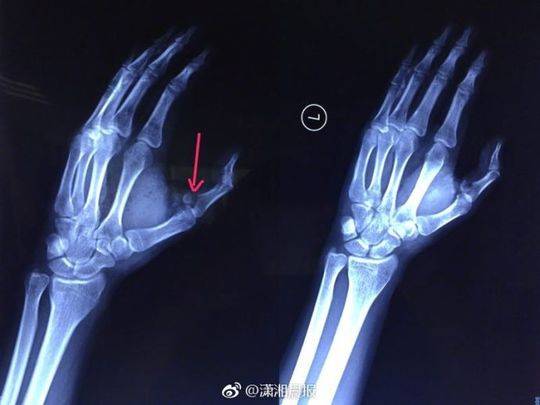

剧烈的疼痛让小袁发出惨叫,家人闻讯赶来一看,只见他的伤口血流不止,受伤的左手也动弹不得,随即将他送往湖南省人民医院急诊一科就诊,医生为其伤口进行了紧急处理。X光检查发现,小袁的左手拇指近节指骨骨折,需进行手术固定,于是将他收入创伤骨病科病房。

当晚10点,该院创伤骨病科何畔副主任医师等为小袁施行" 左手清创探查、左拇指近节指骨骨折切开复位+ 克氏针内固定术",手术历时2小时顺利完成。术后,小袁的左手需采用石膏固定4~6周。